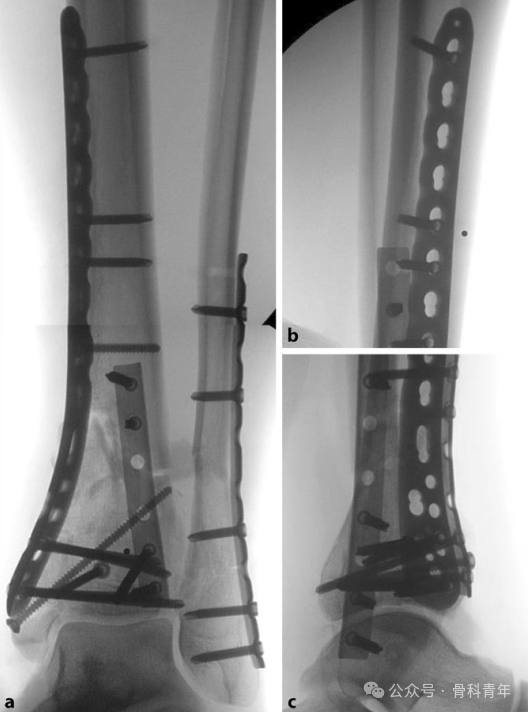

恢复腓骨长度; -

恢复胫骨远端关节面平整; -

胫骨干骺端植骨; -

胫骨内侧钢板固定。